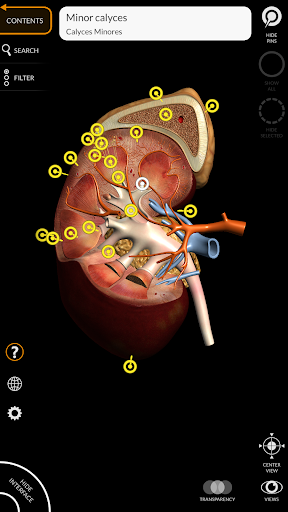

"Anatomy 3D Atlas" memungkinkan Anda mempelajari anatomi manusia dengan cara yang mudah dan interaktif.

Melalui antarmuka yang sederhana dan intuitif, Anda dapat mengamati setiap struktur anatomi dari sudut mana pun.

Model 3D anatomi sangat terperinci dan memiliki tekstur hingga resolusi 4k.

MODEL ANATOMI 3D

saraf • Sistem pernapasan • Sistem pencernaan • Sistem urogenital (pria dan wanita) • Sistem endokrin • Sistem limfatik • Sistem mata dan telinga FITUR • Antarmuka yang sederhana dan intuitif • Putar dan perbesar setiap model dalam ruang 3D • Opsi untuk menyembunyikan atau mengisolasi satu atau beberapa model yang dipilih • Filter untuk menyembunyikan atau menampilkan setiap sistem • Fungsi pencarian untuk menemukan setiap bagian anatomi dengan mudah • Fungsi penanda untuk menyimpan tampilan khusus • Rotasi cerdas yang menggerakkan pusat rotasi secara otomatis • Fungsi transparansi • Visualisasi otot melalui tingkat lapisan dari yang superfisial hingga yang terdalam • Dengan memilih model atau pin, istilah anatomi terkait akan muncul • Deskripsi otot: asal, • Tampilkan/ Sembunyikan antarmuka UI (sangat berguna dengan layar kecil) MULTIBAHASA • Istilah anatomi dan antarmuka pengguna tersedia dalam 11 bahasa: Latin, Inggris, Prancis, Jerman, Italia, Portugis, Turki, Rusia, Spanyol, Mandarin, Jepang, dan Korea • Istilah anatomi dapat ditampilkan dalam dua bahasa secara bersamaan PERSYARATAN SISTEM • Android 8.0 atau yang lebih baru, perangkat dengan RAM minimal 3GB Reversi